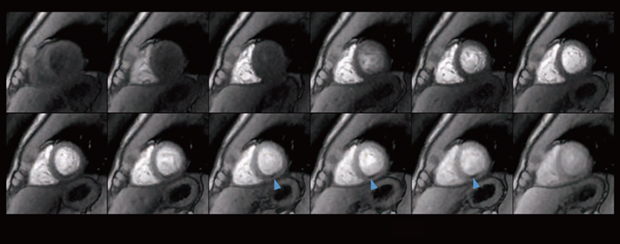

現在,GE HealthCare(GEHC)のMRシステムの最新バージョンである30.1には,用途の異なる2つのディープラーニング画像再構成技術がある。高速撮像に特化した「Sonic DL」は,物理駆動型ディープラーニングアルゴリズムを用いた高速撮像専用の技術で,心臓シネ撮像時に使用できる。Sonic DLは,最大12倍速のアクセラレーション設定が可能で,画像劣化を最小限に抑えながら高品質な画像を生成できる。シネ撮像の高速化により,1回の呼吸停止で複数スライスのシネ撮像が可能となる。それにより,左室短軸像を取得する際の呼吸停止回数を削減し,検査時間を短縮することで,患者の負担を大幅に軽減できるようになった(図1 a,b)。

図1 ディープラーニング画像再構成による画質改善効果

a:従来のシネ撮像(1.8mm×1.8mm×6mm,3:45)

b:Sonic DLによるシネ撮像(1.8mm×1.2mm×6mm,1:55)